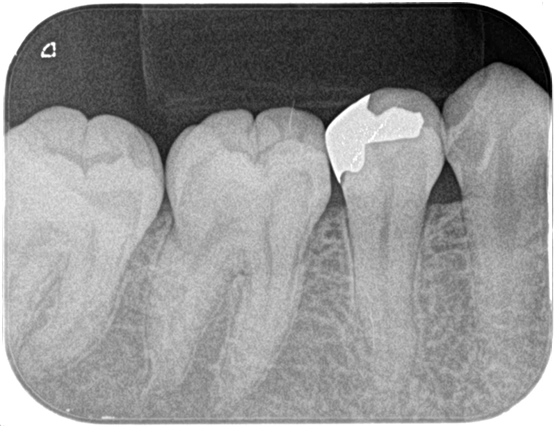

根管治療 症例9

| 治療前 | ![]() |